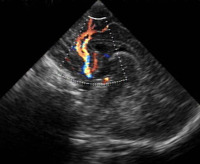

- Ein Risikofaktor für den plötzlichen Säuglingstod ist eine Minderversorgung des Hirnstammes durch verminderten Blutfluß in einem wichtigen Blutgefäß bei Kopfwendung des Säuglings (Arteria basilaris bzw. Arteria vertebralis).

- Eine Doppler-Sonographie der entsprechenden Arteria basilaris wird bei uns angeboten: der optimale Untersuchungszeitpunkt liegt in der frühen Säuglingszeit ab Vorsorge U2 bis U3.